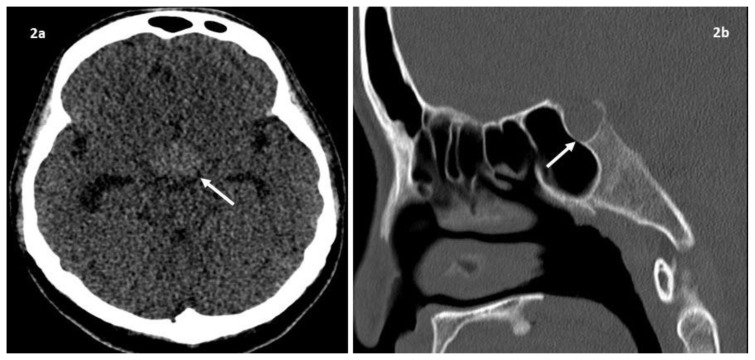

Figure 2.

59-year-old lady with clival chordoma.

Findings: (a) Non-contrast axial CT image shows the sellar/suprasellar mass is slightly hyperdense to the brain parenchyma. (b) Sagittal reformatted CT image in the bone window shows mild erosion of the dorsum sellae and thinning of the sellar floor.

Technique: Siemens SOMATOM Definition Flash CT scanner. 120 kV. 67 mAs.

a) Axial soft tissue window. 1mm slice thickness.

b) Sagittal bone window. 3mm slice thickness.

A magnetic resonance imaging (MRI) of the brain found a lobulated mass in the sellar and suprasellar regions measuring 1.9 × 2.1 × 3.8 cm (anteroposterior × transverse × craniocaudal dimensions) (fig. 1). The mass showed intermediate signal intensity on T1-weighted images and high signal intensity on T2-weighted images. There was homogenous enhancement of the mass on post contrast images. Susceptibility artefacts within the mass were indicative of hemorrhagic foci or calcifications. The optic chiasm was displaced posterolaterally due to mass effect. The mass was closely related to the cavernous sinuses with no evidence of tumor invasion. Areas of abnormal marrow signal with contrast enhancement were noted in the dorsum sellae and clivus on the MRI. Computed tomography (CT) showed a hyperdense sellar/suprasellar mass with irregularity of the dorsum sella turcica and thinning of the sellar floor suggesting erosion (fig. 2). The mass was presumed to be a pituitary macroadenoma, as the normal pituitary gland was not visualized on MRI.